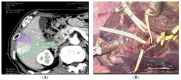

Laparoscopic liver resections have gained widespread popularity among hepatobiliary surgeons and is nowadays performed for both standard and more complex hepatectomies. Given the increased technical challenges, preoperative planning and intraoperative guidance is pivotal in laparoscopic surgery to safely carry out complex and oncologically safe hepatectomies. Modern tools can help both preoperatively and intraoperatively and allow surgeons to perform more precise hepatectomies. Preoperative 3D reconstructions and printing as well as augmented reality can increase the knowledge of the specific anatomy of the case and therefore plan the surgery accordingly and tailor the procedure on the patient. Furthermore, the indocyanine green retention dye is an increasingly used tool that can nowadays improve the precision during laparoscopic hepatectomies, especially when considering anatomical resection. The use of preoperative modern imaging and intraoperative indocyanine green dye are key to successfully perform complex hepatectomies such as laparoscopic parenchymal sparing liver resections. In this narrative review, we discuss the aspects of preoperative and intraoperative tools that are nowadays increasingly used in experienced hepatobiliary centers.